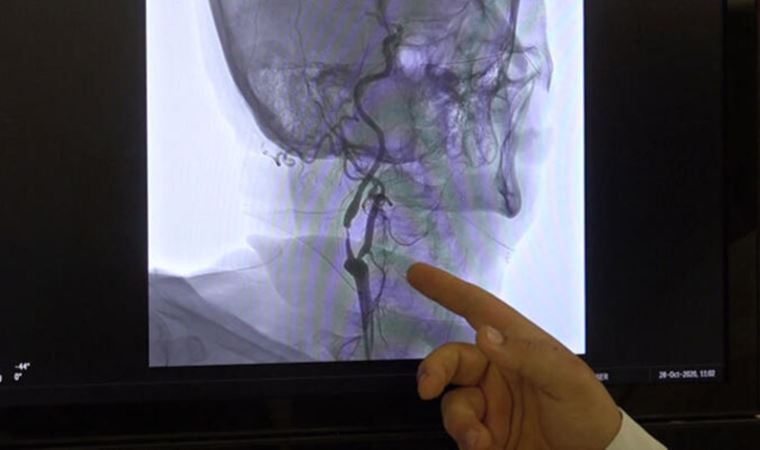

Kanamadan şüphelenilecek durumlardan da kısaca bahseden Prof. Dr. Bayram Çırak, “Kanamadan şüphelenilecek durumlardan ani ve oldukça şiddetli olan bir baş ağrısı en sık rastlanan belirtilerdendir. ‘Kafamın içinde bomba patladı sanki’ der hasta, bunlar yüksek tansiyon, damar bozukluğu, kan sulandırıcı ilaç kullanımı öyküsü olanlarda sık rastlanır. Ani oluşan bilinç değişikliği, şuur kaybı, konuşma bozukluğu, havale geçirme, gözlerde ve yüzde kayma, motor duyu değişiklikleri yani el, kol veya bacaklarda tutmama, güçsüzlük, dengesizlik, bulantı, kusma, ani başlayan unutkanlık, okuma-yazma bozukluğu şeklinde sıralayabiliriz. Beyin kanaması muayene bulguları ile her zaman tanı koymak mümkün olmayabilir. Bu nedenle acil yapılabilecek en güzel tetkik bilgisayarlı tomografidir (BT). İlk kanama tanısı BT ile yapılır. Ancak ayırıcı tanı gerekirse yani beyinde kanama yapacak herhangi bir damar bozukluğu anevrizma, baloncuk veya damar yumağı var mı diye bakılır. Kanamanın ayrıntılarını görüntülemek amacıyla ileri tetkikler gerekebilir. Bunlar arasında manyetik rezonans görüntüleme (MR), anjio ile beyin damarlarının görüntülenmesi önemlidir. Küçük çocuklarda özellikle bıngıldak kapanmadığı dönemde kafa ultrasonu hem tanı hem takipte oldukça yararlı ve hastaya zararı olmayan bir tetkiktir” şeklinde bilgi verdi.